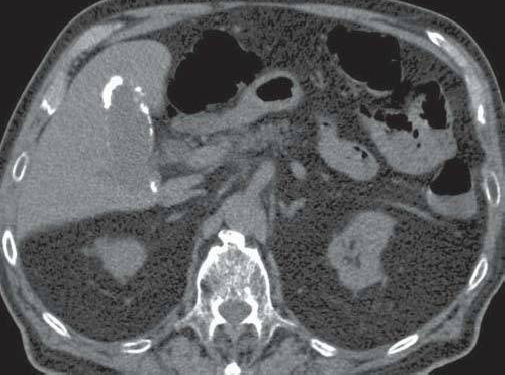

CT表现:胆囊壁呈均匀或不均匀的环状、条状或斑点状高密度影

I型:胆囊壁完全环形钙化

II型:胆囊壁呈部分曲线状钙化

III型:胆囊壁散在斑点状钙化

患者某,女,80岁,因右上腹绞痛,伴呕吐几小时就诊,病人经保守治疗症状消失,离开急诊科,一个月后,突发黄疸、弥漫性腹痛,伴发热、寒战再次就诊。